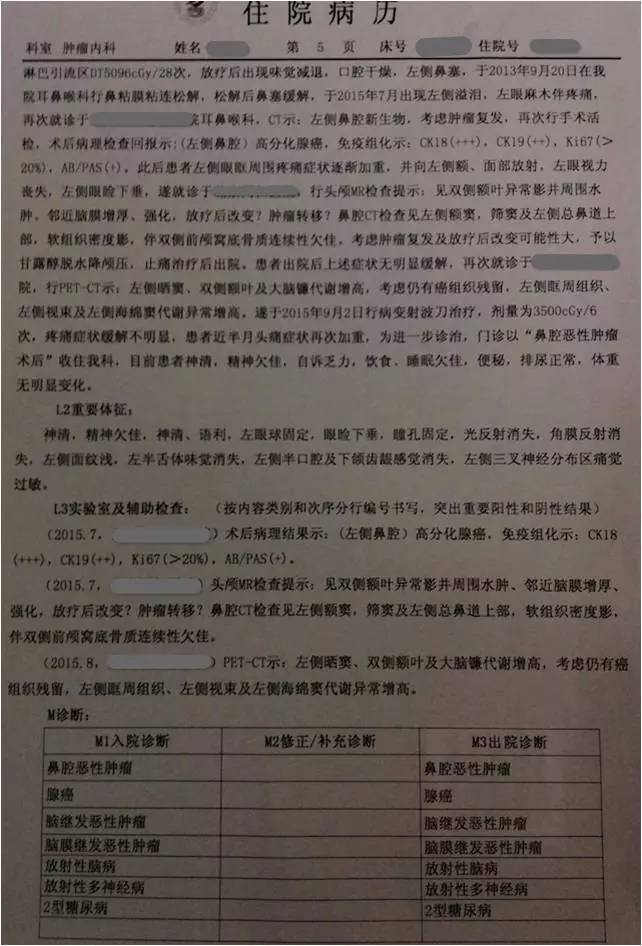

▼患者病情描述

复习病史,患者2013-7鼻内镜鼻腔肿物切除术,病理高分化腺癌,术后行同期放化疗,鼻腔局部照射65.72Gy/31f;2015-7出现前组脑神经损害症状体征,影像检查提示鼻腔及筛窦、额窦肿物,伴前颅底额叶异常强化及周围水肿,局部脑膜增厚、强化,颅底骨质不连续,考虑复发伴放射性改变;经鼻腔再次活检证实为复发;给予对症治疗症状加重,遂行PET/CT提示筛窦、双侧额叶、大脑镰、左侧眶周、海绵窦代谢增高;局部行射波刀治疗35Gy/6f,具体不详;疗后症状无明显缓解。首先双侧额叶改变MRI不能区别放射性脑坏死和肿瘤复发,可考虑进一步MRS、PWI、DWI成像提供更多的信息鉴别两者;倾向于肿瘤复发可能性大,原因如下:病变范围可能远远超出照射野;距放疗时间较短,文献报道一般放射性脑坏死中位发生时间约6年;颅底骨质破坏伴代谢增高,且与鼻腔、筛窦、左眶、海绵窦代谢一致。当然也不排除同时合并放射性损害,毕竟同时行化疗,可能较单纯放疗反应重。关于是否再行放疗改善症状,取决于前2次放疗的评价,看危及器官尤其是脑干、健侧视神经是否还能耐受;可使用卡马西平0.1、Tid,可能减轻神经痛症状;对症支持治疗方面适当应用激素、甘露醇等减轻脑水肿;也可考虑联合贝伐单抗;后续肿瘤治疗以化疗为主,请Z主任斟酌方案。